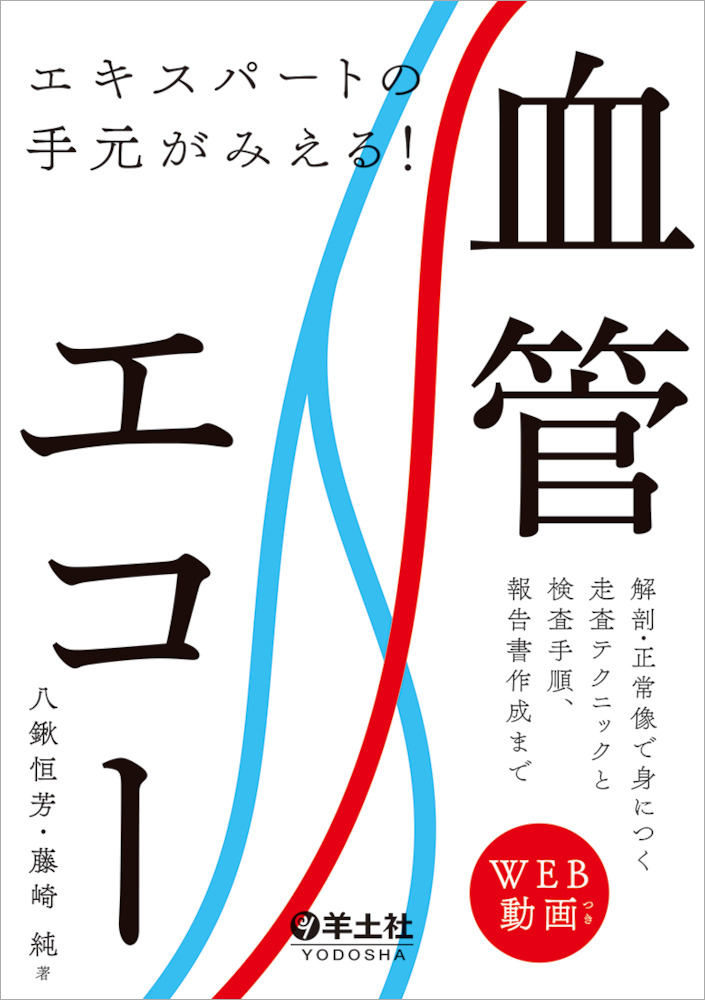

Amazon.co.jp: エコーを使ったバスキュラーアクセス穿刺法ガイド。エキスパートの手元がみえる!血管エコー〜解剖・正常像で身に。Amazon.co.jp: 超音波ガイド下穿刺トレーニングゲル UGP-GEL F。

「血管エコ-パ-フェクトガイド」

エコーを使ったバスキュラーアクセス穿刺法ガイド | 木船 和弥